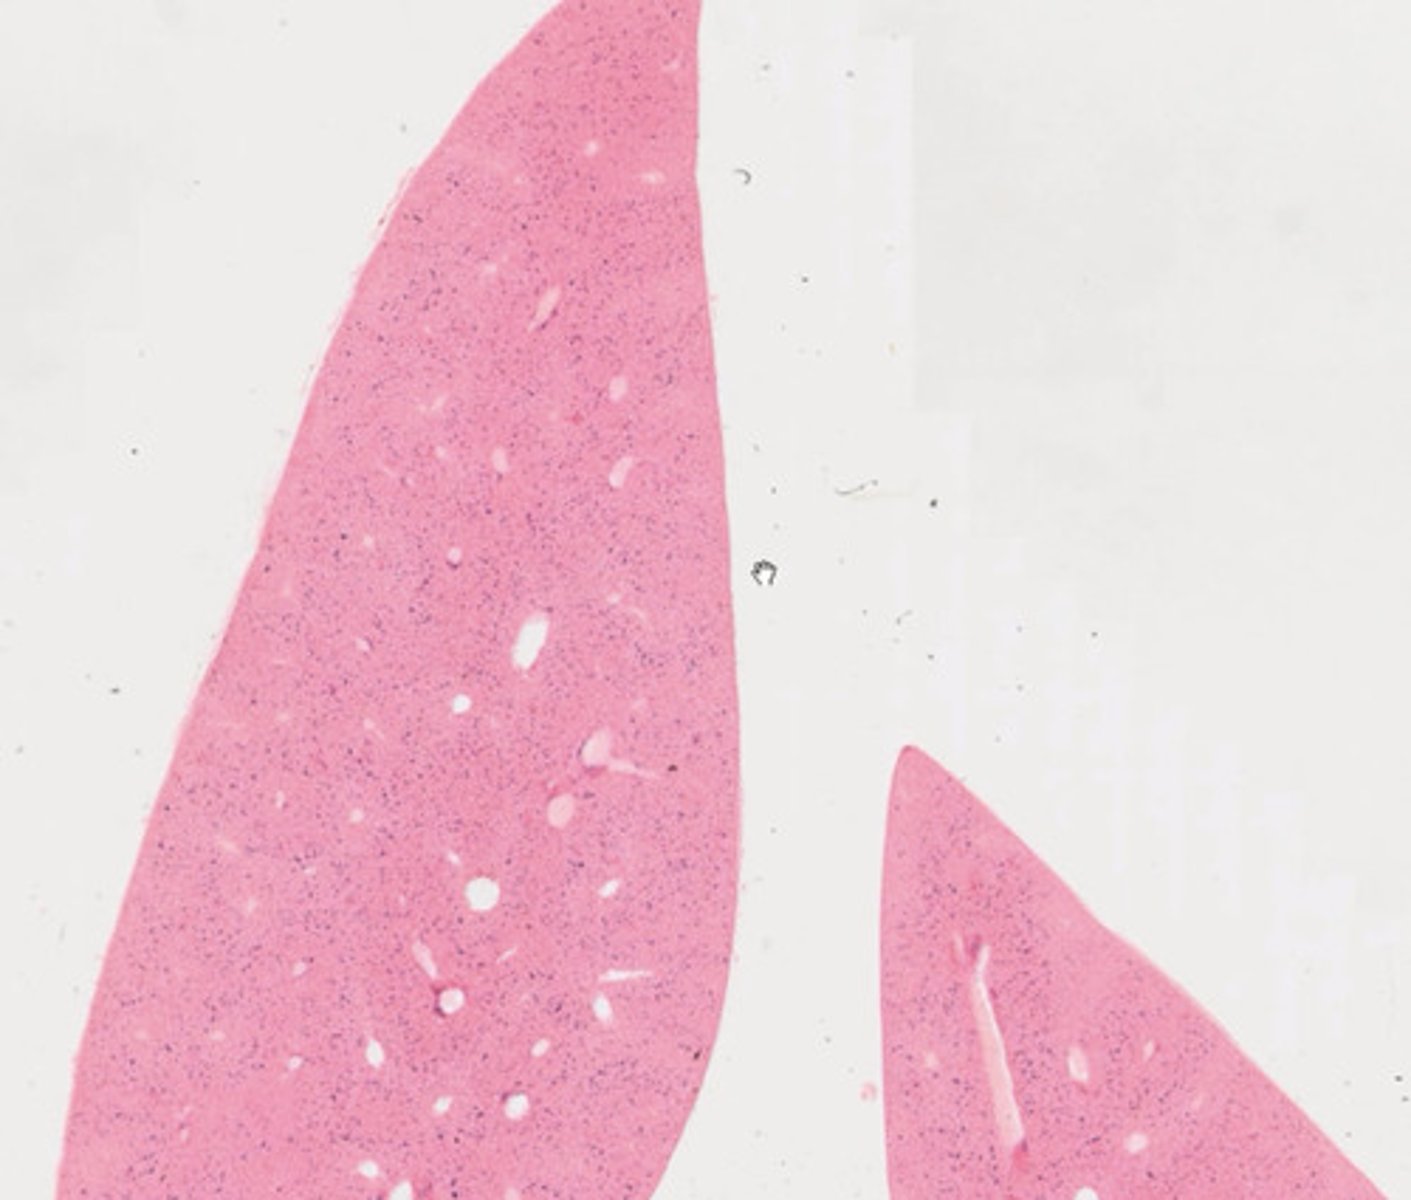

Móżdżek (H+E)